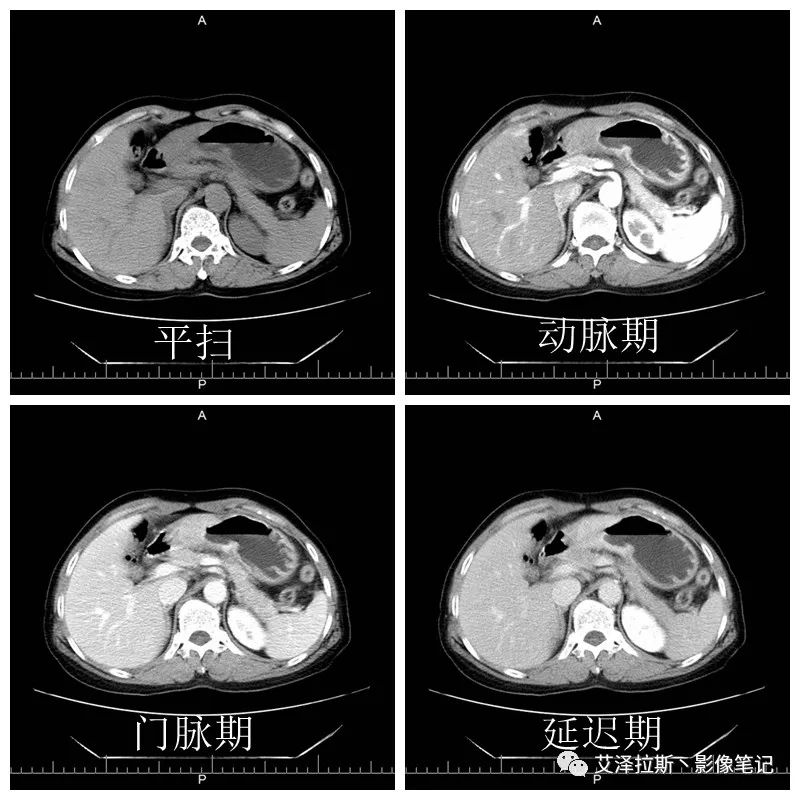

圖1 平掃+增強各期

【影像所見】 胃竇部狹窄,胃壁環形增厚,小彎側見一巨大潰瘍,周圍伴“環堤征”,漿膜面不完整,胃周脂肪見網格狀條索影,病灶與肝臟左葉、胰腺鉤突脂肪間隙消失,增強掃描病灶明顯強化。引流區內約15個區域淋巴結受累。

【診斷意見】 胃竇部胃癌(T4N3期) 該病例腫塊突破漿膜層,與肝臟左葉、胰腺鉤突分界不清,脂肪界面消失,定為T4期; 受累及的淋巴結為15個區域,定為N3; 有無遠處轉移尚不明確,所以M期暫時無法確定。